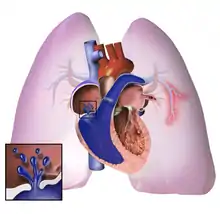

The pathogenesis of pulmonary arterial hypertension (WHO Group I) involves the narrowing of blood vessels connected to and within the lungs. This makes it harder for the heart to pump blood through the lungs, as it is much harder to make water flow through a narrow pipe as opposed to a wide one. Over time, the affected blood vessels become stiffer and thicker, in a process known as fibrosis. The mechanisms involved in this narrowing process include vasoconstriction, thrombosis, and vascular remodeling (excessive cellular proliferation, fibrosis, and reduced apoptosis/programmed cell death in the vessel walls, caused by inflammation, disordered metabolism and dysregulation of certain growth factors).[26][27] This further increases the blood pressure within the lungs and impairs their blood flow. In common with other types of pulmonary hypertension, these changes result in an increased workload for the right side of the heart.[15][28] The right ventricle is normally part of a low pressure system, with systolic ventricular pressures that are lower than those that the left ventricle normally encounters. As such, the right ventricle cannot cope as well with higher pressures, and although right ventricular adaptations (hypertrophy and increased contractility of the heart muscle) initially help to preserve stroke volume, ultimately these compensatory mechanisms are insufficient; the right ventricular muscle cannot get enough oxygen to meet its needs and right heart failure follows.[15][27][28] As the blood flowing through the lungs decreases, the left side of the heart receives less blood. This blood may also carry less oxygen than normal. Therefore, it becomes harder and harder for the left side of the heart to supply sufficient oxygen to the rest of the body, especially during physical activity.[29][30][10] During the end-systolic volume phase of the cardiac cycle, the Gaussian curvature and the mean curvature of right ventricular endocardial wall of PH patients was found to be significantly different as compared to controls.[31]

In PVOD (WHO Group I'), pulmonary blood vessel narrowing occurs preferentially (though not exclusively) in post-capillary venous blood vessels.[32] PVOD shares several characteristics with PAH, but there are also some important differences, for example differences in prognosis and response to medical therapy.